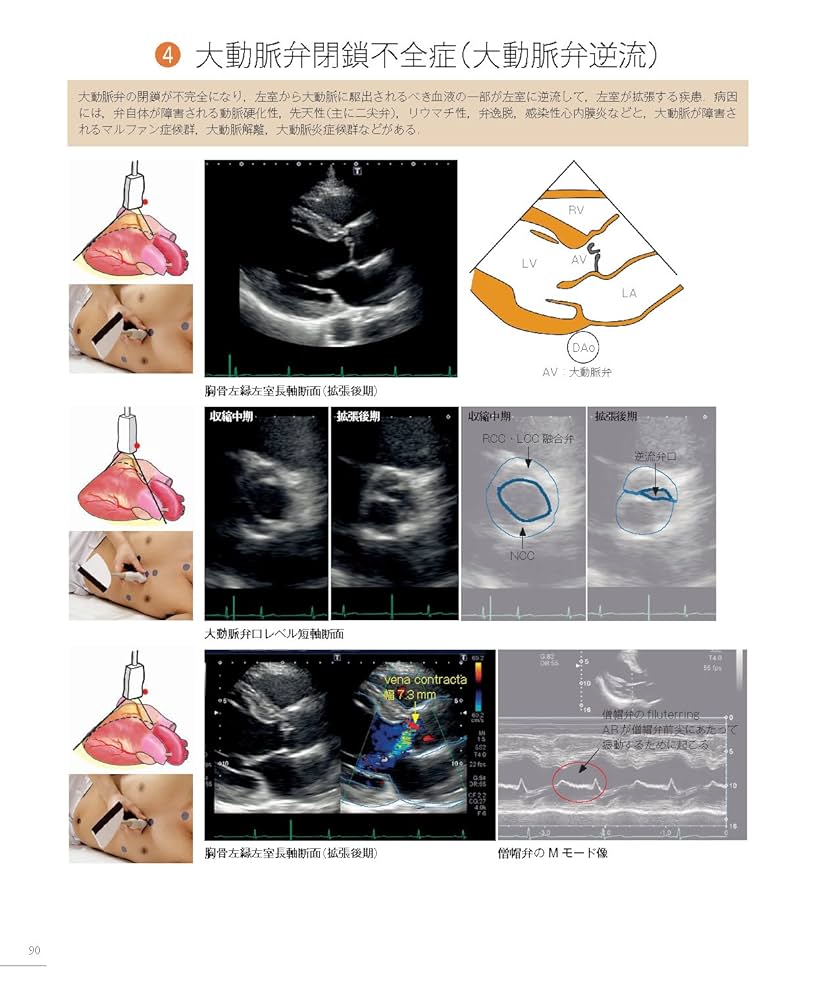

• 疾患と異常像がわかる! エコーの撮り方 完全マスター | 種村 正

• 解剖と正常像がわかる!—エコーの撮り方 完全マスター (検査と